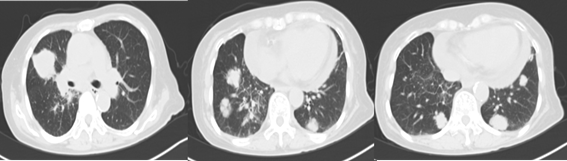

2020.6 胸部双源增强CT:双肺多发大小不等肿块,大者约39*40mm,位于右肺中叶,增强扫描边缘强化。纵隔内见肿大的淋巴结。

2020.11 胸部双源增强CT:双肺多发大小不等肿块,大者约29*52mm,位于右肺中叶,增强扫描边缘强化,部分病灶内见空洞,右肺中叶不张,右肺中叶支气管闭塞。双肺散在条索灶。右肺上叶间质改变。